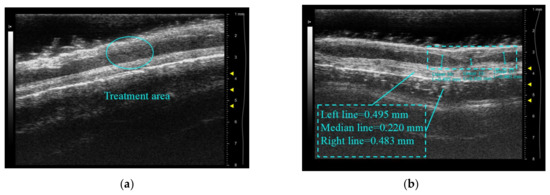

Figure 15 displays a comparison of vascular imaging before and after treatment of the inferior tube wall using a commercial Vevo 2100 small animal ultrasound system in combination with a 50 MHz center frequency linear array imaging probe. The untreated porcine artery area in Figure 15a is approximately 6.54 mm2, with a maximum diameter of 3.143 mm and a minimum diameter of 2.648 mm. The treated pig artery section is displayed in Figure 15b, with an area of approximately 4.898 mm2, a maximum diameter of 3.027 mm, and a minimum diameter of 1.987 mm. The cross-sectional area decreases by 25% after the treatment, while the minimum diameter decreases by 24%. The inferior wall of the vessel indicates notable shrinkage, consistent with the result of the high-light denaturation on the inferior surface of the vessel after treatment in Figure 14c, thereby confirming the effectiveness of this innovative high-frequency ultrasound-guided integrated system for varicose vein ultrasound therapy under similar working conditions.

Figure 15.

Cross-sectional ultrasound comparison images of blood vessels before and after treatment: (a) before treatment; (b) after treatment.